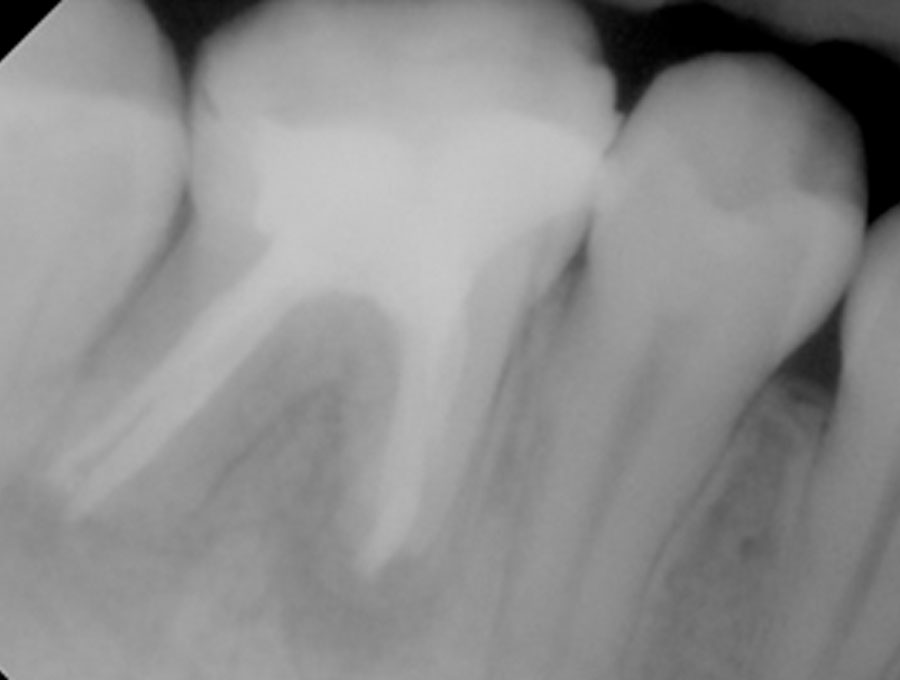

Ατελής ενδοδοντική θεραπεία που οδήγησε σε περιακρορριζική καταστροφή.

Η επανάληψη της ενδοδοντικής θεραπείας δεν οδήγησε σε πλήρη επούλωση της βλάβης,

καθώς είναι αναγκαία και η περιοδοντική θεραπεία του δοντιού.

Χρόνια φλεγμονώδης περιακρορριζική βλάβη, κυρίως,

λόγω ενδοδοντικής αιτιολογίας. Μετά την ενδοδοντική θεραπεία

ακολούθησε περιοδοντική θεραπεία.

Δύο χρόνια μετά, παρατηρείται πλήρης εξαφάνιση της βλάβης.